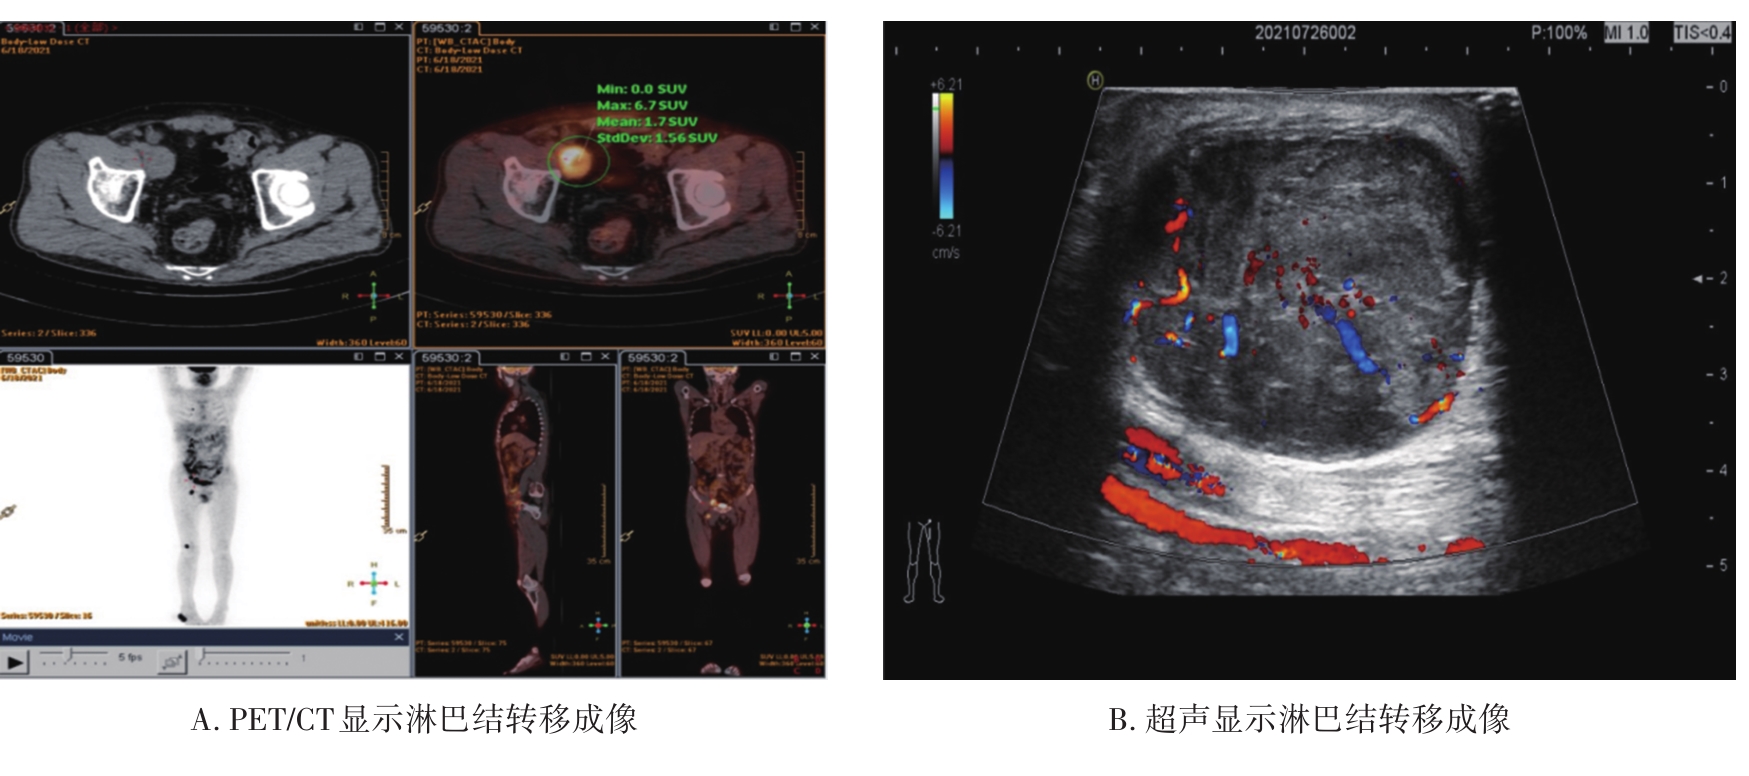

• 超声、PET/CT及两者联合检测对恶性黑色素瘤淋巴结转移的临床价值分析

摘要:目的 探讨超声、正电子发射断层成像/计算机断层成像(positron emission tomography/computed tomography,PET/CT)及两者联合检测对恶性黑色素瘤(malignant melanoma,MM)淋巴结转移评估的准确性,指导临床MM患者淋巴结活检及清扫的术前评估。方法 收集41例MM住院患者临床资料,分析术前淋巴结相关影像资料、术后淋巴结病理结果及病理结果跟影像结果的相关性。结果 超声、PET/CT以及两者联合检测的敏感度分别是47.36%、73.68%、78.95%,特异度分别是59.09%,86.36%、50.00%,准确度分别是53.66%、80.49%、63.41%,阳性预测值分别是50.00%、82.35%、57.69%,阴性预测值分别是56.52%,79.17%、73.33%,正确指数分别是6.45%、60.04%、28.95%。结论 PET/CT在评估MM术前淋巴结是否转移方面具有重要价值,其准确度、特异度、阳性预测值、阴性预测值均高于超声及两者联合检测,当PET/CT检查淋巴结转移为阴性时,应结合超声两者联合综合判断,避免淋巴结转移漏诊,提高淋巴结转移检出率,使MM患者早诊断、早治疗,从而获得最佳治疗效果。影像学虽然不能作为诊断标准和最终依据,但可指导临床行淋巴结活检手术前的评估,减少漏诊。